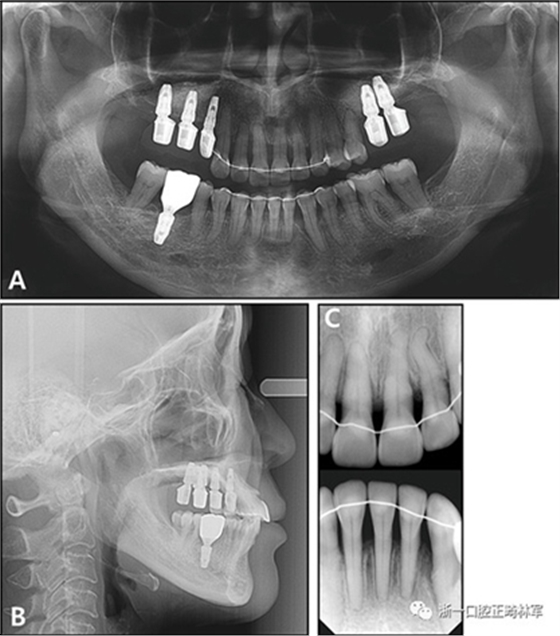

全景X線片顯示了牙槽骨支持的整體下降和下頜左側側切牙區(qū)廣泛的骨質喪失。頭影測量分析表明是具有正常垂直面形,上頜切牙唇向錯位以及與Rickett‘s E線相關的上唇前凸的骨性I類關系(圖3和4;表II)?;颊弑辉\斷為骨骼I類錯合畸形,伴有慢性中度牙周炎和多顆牙齒缺失。

圖3. 治療前X線片:A,牙周治療前的全景X光片; B,牙周治療后的全景X光片; C,側位X線片; D,根尖片。

治療后全景X線片顯示與初始值相比,沒有顯著的骨喪失。上頜尖牙被推入并向遠中移動,導致在根尖周觀察到尖牙骨水平的改善。在拔除的下頜側切牙周圍出現(xiàn)嚴重的牙槽骨缺損,并且尖牙近中側的牙周病引起了骨內缺損。在關閉間隙期間,下頜中切牙和尖牙被移向了骨質缺損區(qū)域,并且側切牙周圍的缺損已被恢復(圖12)。此外,尖牙的牙齦退縮臨床上也得到了改善(圖13)。

圖12.治療后的X線片:A,全景X光片;B,頭影側位片;C,根尖片